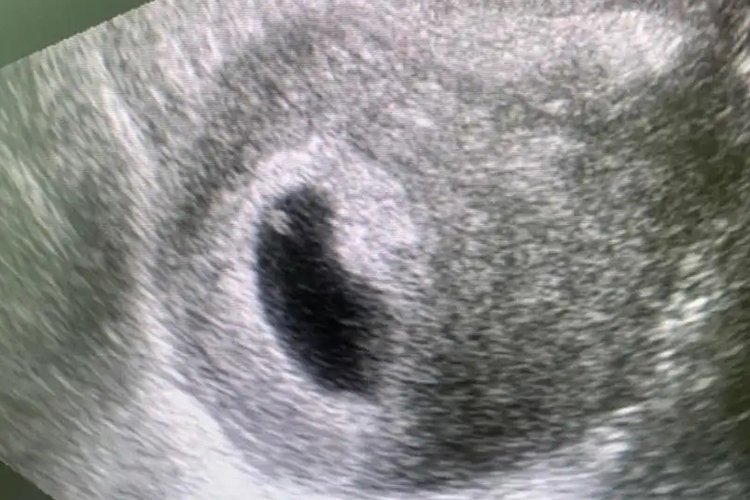

B超检查中在胚点或胚芽一旁显示的一小圆形囊状结构即为卵黄囊,直径3-8mm。妊娠5周时卵黄囊较为清晰,妊娠10周后可逐渐萎缩消失。早期卵黄囊紧贴胚胎上,后期以一条细带与胎儿脐部相连。一般情况下,卵黄囊清晰、大小正常可推断胚胎良好。

B超下的卵黄囊为圆形囊状结构,局部较为清晰。卵黄囊的存在及大小对于诊断早孕胚胎,或判断先兆流产的预后具有一定临床意义。